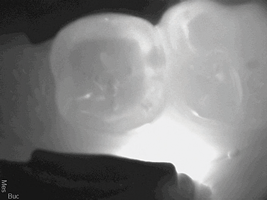

A 56-year-old female patient required an extensive treatment plan, including multiple crowns and fillings in each quadrant. She was able to complete treatment only in stages. By the time one quadrant was completed, she began to have pain on the mesial of tooth No. 20 (Figure 1 and Figure 2). Because the patient had no more dental benefits for the year, she needed to alleviate the sensitivity and prevent further problems between appointments. The doctor recommended SDF to stave off the sensitivity she was experiencing and to prevent growth of the lesion. Silver diamine fluoride was placed during a restorative appointment, and her sensitivity and pain subsided. When she returned a month later for her hygiene visit, she stated her pain had returned. A second SDF treatment was administered, which prevented the pain from returning a third time, until her restorative treatment could resume.

(1.) Patient exhbitied pain on the mesial of tooth No. 20.

Figure 1

(2.) Patient required an extensive treatment plan, including multiple crowns and fillings in each quadrant.

Figure 2